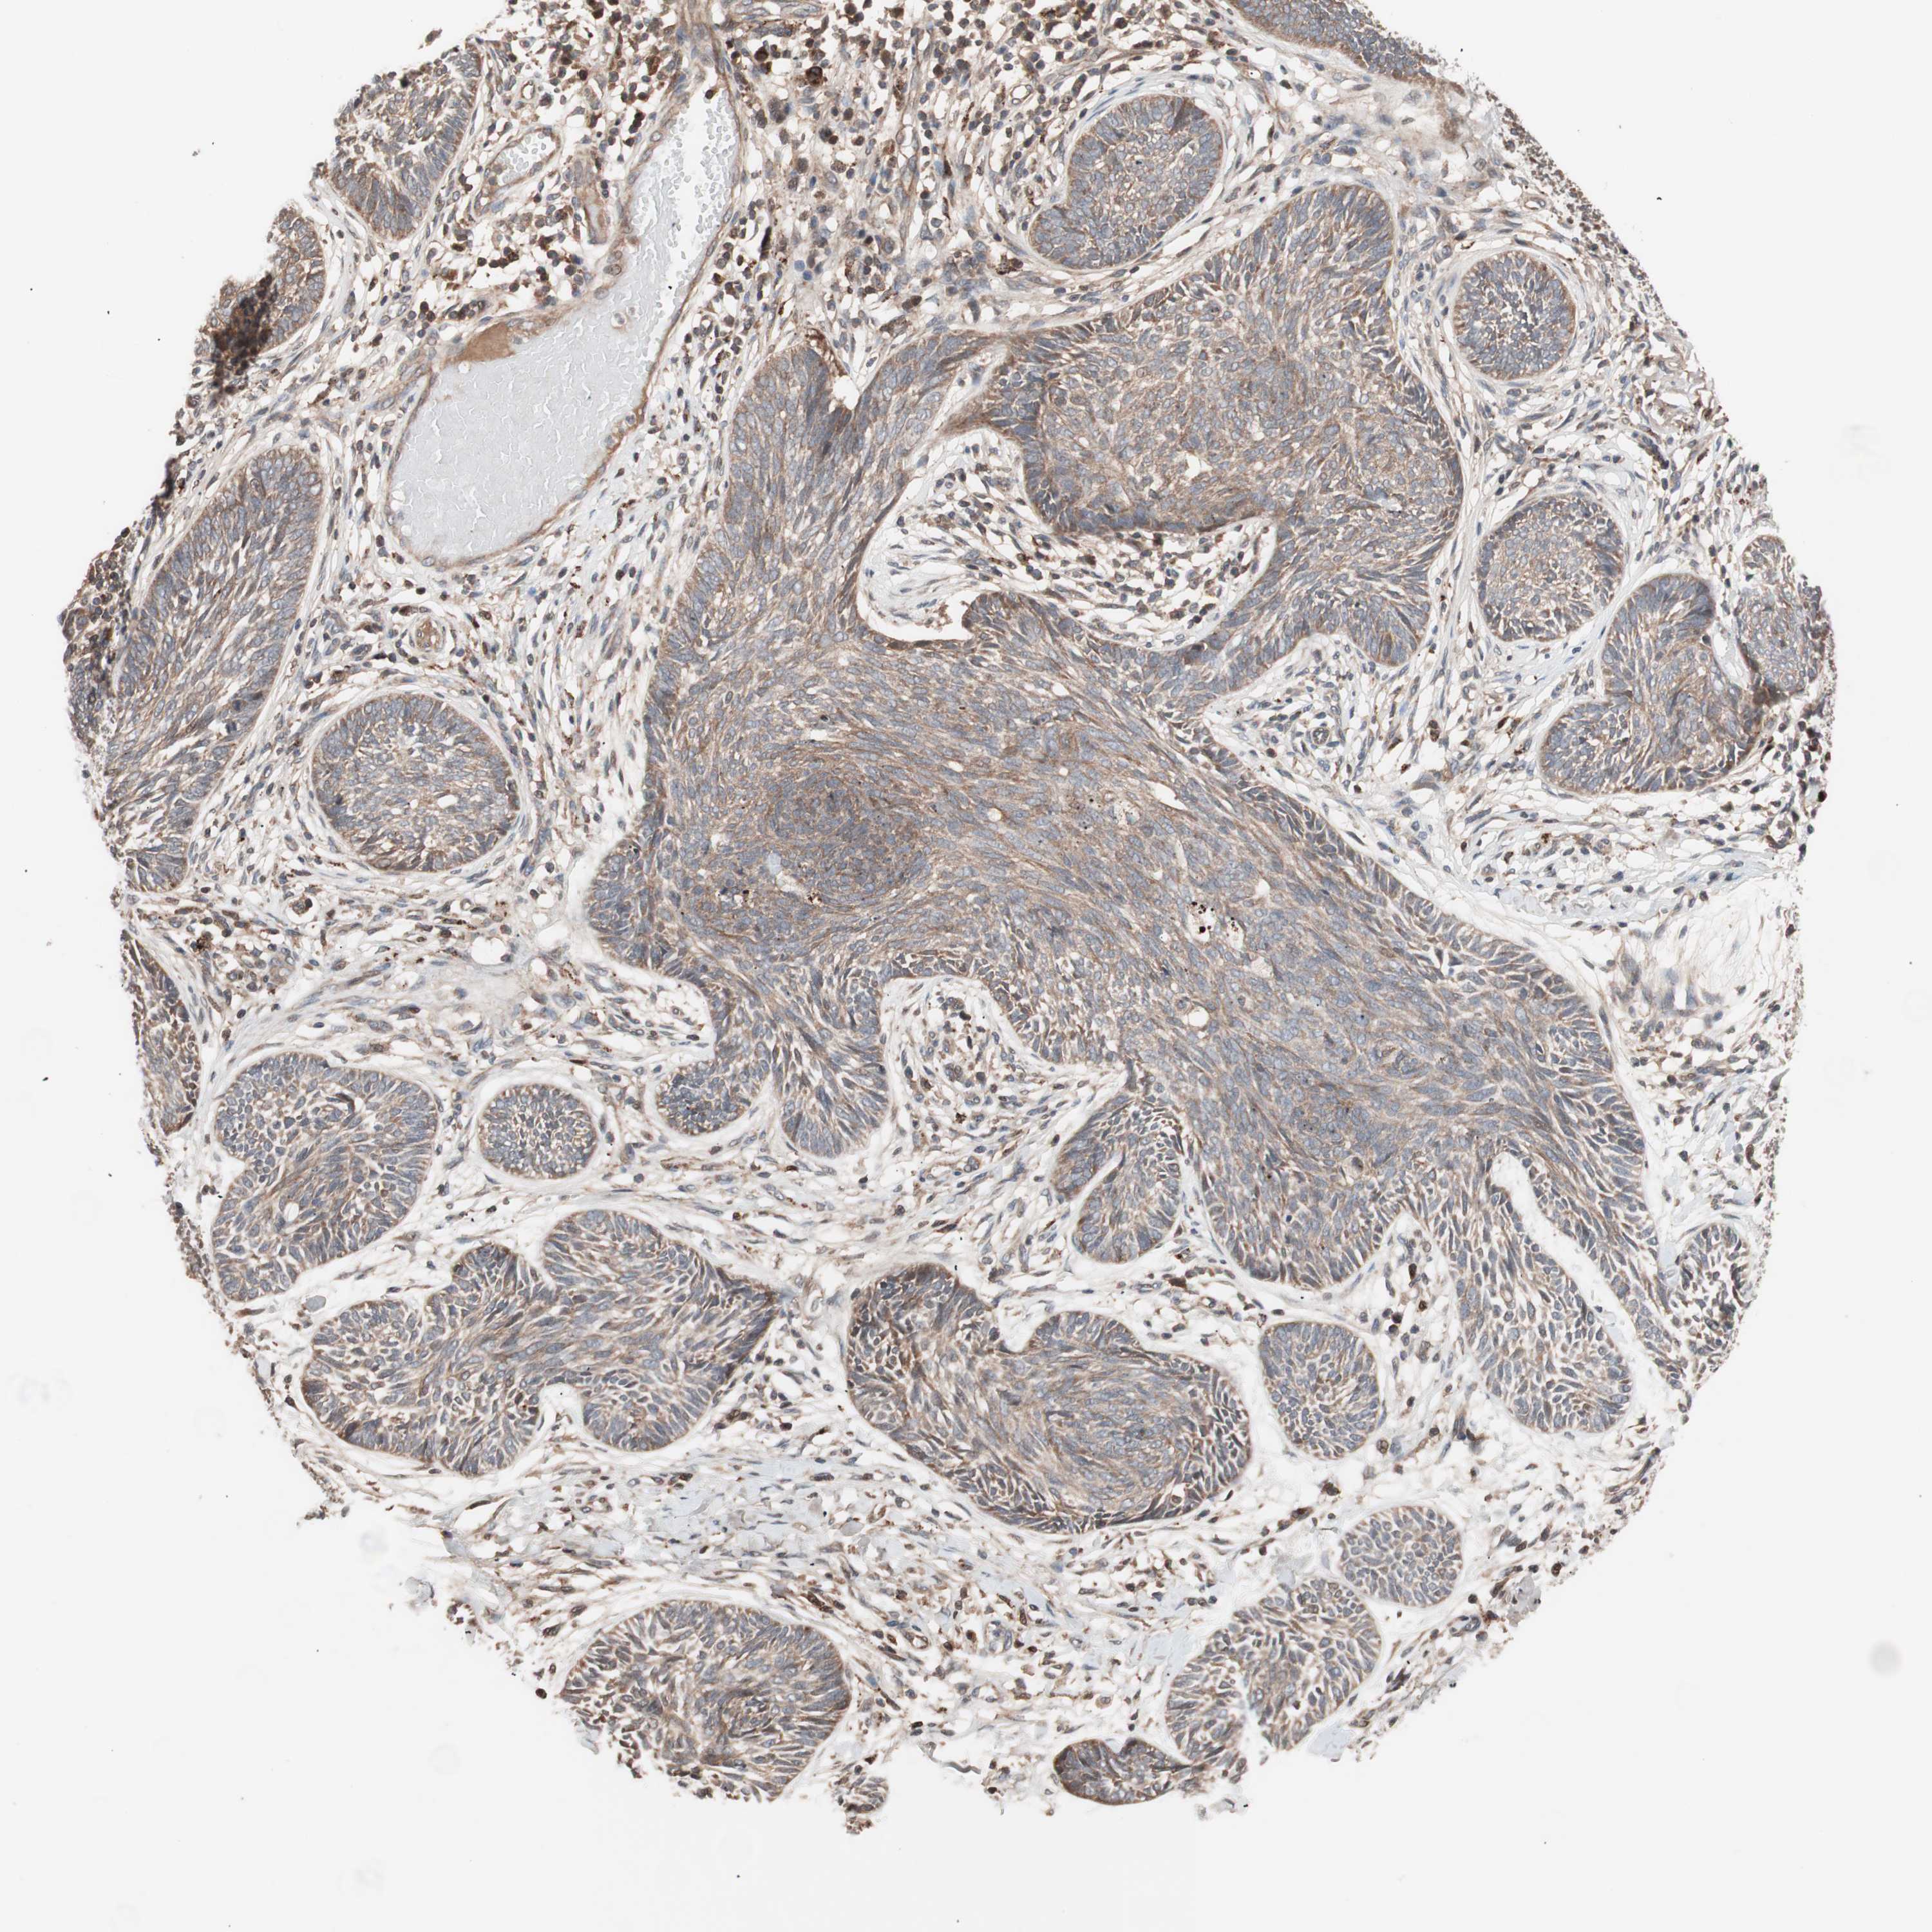

SKIN CANCER - Protein expressioni

A mouse-over function shows sample information and annotation data. Click on an image to view it in a full screen mode. Samples can be filtered based on level of antibody staining by selecting one or several of the following categories: high, medium, low and not detected. The assay and annotation is described here.

Antibody stainingi

Antibody staining in the annotated cell types in the current human tissue is reported as not detected, low, medium, or high, based on conventional immunohistochemistry profiling in selected tissues. This score is based on the combination of the staining intensity and fraction of stained cells.

Each image is clickable and will lead to virtual microscopy that enables deeper exploration of all samples and also displays staining intensity scores, fraction scores and subcellular localization as well as patient and tissue information for each sample.

Antibody HPA003097

Antibody CAB005385

Squamous cell carcinoma, NOS

Basal cell carcinoma

Squamous cell carcinoma, metastatic, NOS

Papilloma, NOS